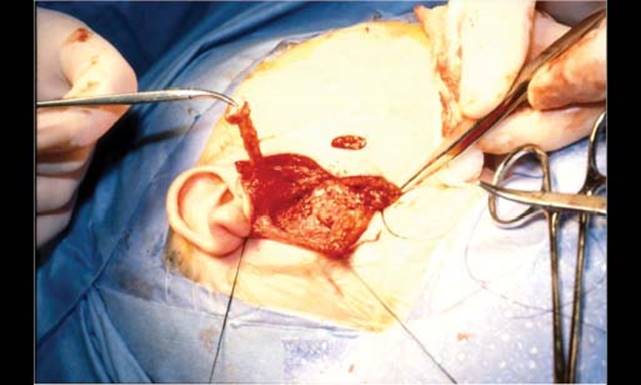

Figure 19.3 Complete excision of first branchial cleft anomalies including facial nerve dissection.

First BAs

Surgical excision of Type I anomalies should include exploration and excision of the mass and its tract down to the EAC at its bony junction (Fig. 19.3). Management of Type II anomalies entails excision via parotidectomy incision and complete excision of the tract. Conservative parotidectomy with identification of the facial nerve is required in most cases. Limited cystectomies will result in recurrence and the incidence of facial nerve injury is higher if the nerve is not identified.4 Facial nerve monitors are often used during these operations, but a thorough knowledge of the relationship of the tracts with the facial nerve is essential. If the sinus tract involves the cartilaginous EAC, it should be marsupialized with an ellipse of cartilage removed.